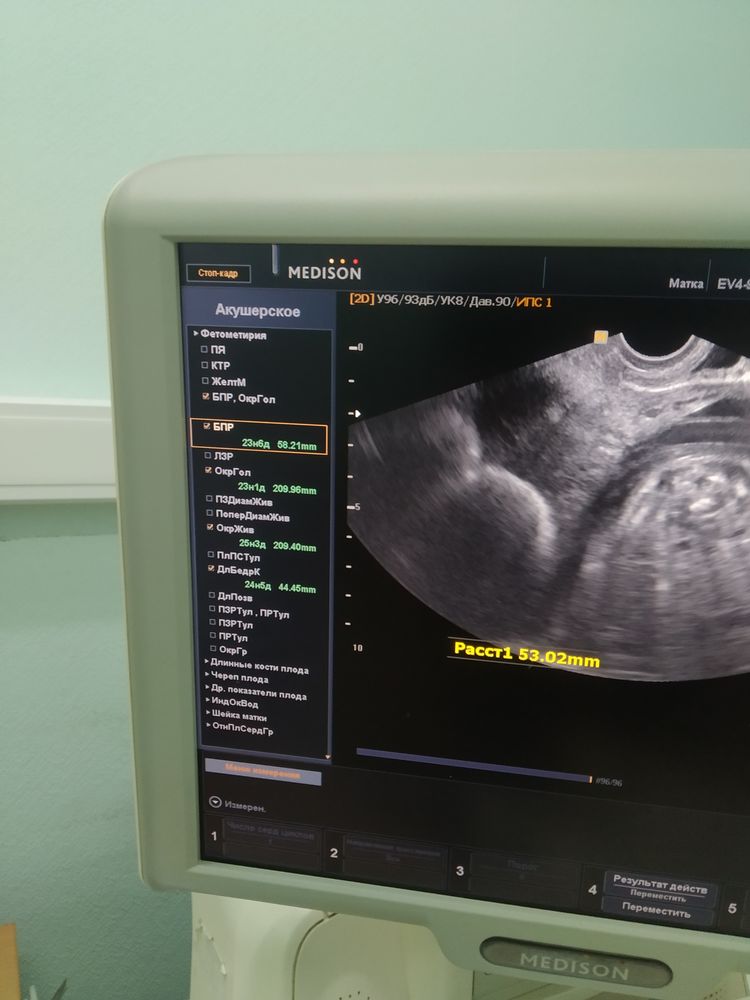

-сказала, что всё размеры ребёнка на срок, но видно же, что написано:

Бпр на 23 и 6

Окр головы на 23 и 1

Окр живота на 25 и 3

Длина бёдра на 24 и 5.

Срок по месячным 24 и 3. Это вообще нормально?